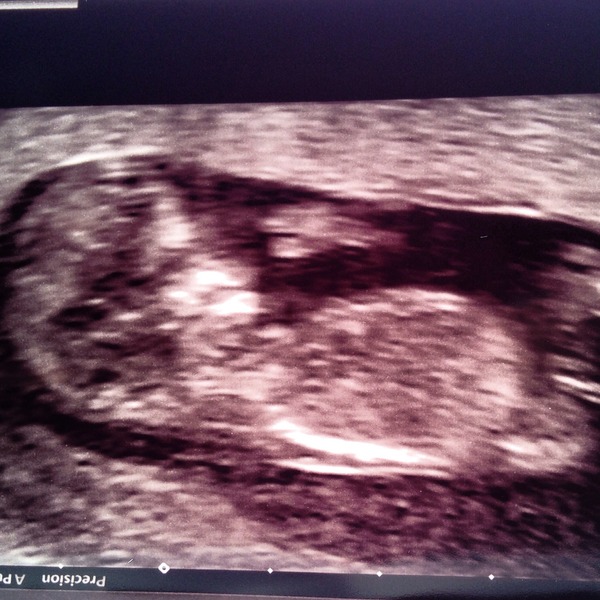

bouncesky · 21/08/2014 22:21

Here's the picture :-) great to see other's scan pictures!